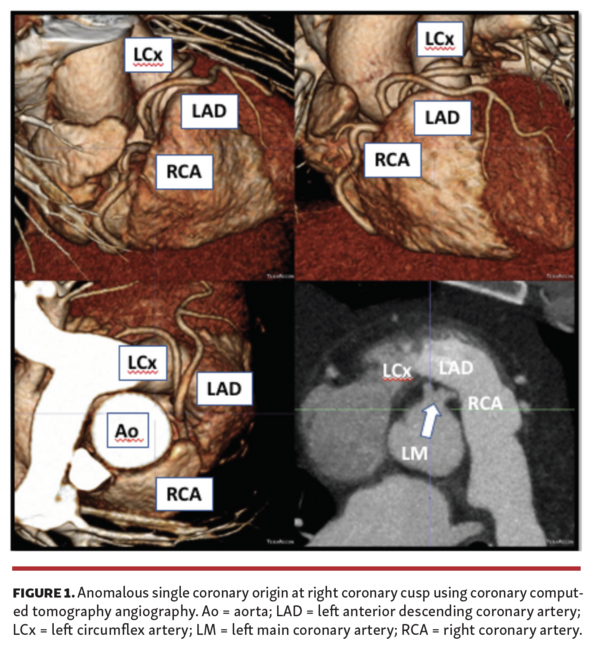

The decision was made to proceed with coronary angiography, which demonstrated anomalous coronary circulation with 1 ostium for all arteries at the site of the right coronary cusp. Vessels were normal caliber and without evidence of disease. The left anterior descending/left circumflex coronary course was not clearly identified and coronary computed tomography angiography (CCTA) was recommended.

CCTA confirmed anomalous common origin anterior to the sinus of Valsalva and the course was prepulmonic (Figure 1). Given the benign prognosis associated with prepulmonic course, the patient was managed conservatively.

Ischemic work-up is important in this group of patients, with coronary angiography being the gold standard. As demonstrated here, CCTA is an essential tool to define artery course and provide further risk stratification. SCAs were originally classified by Lipton et al based on the site of origin and subtypes of anatomical distribution. Some subtypes are higher risk for SCA, especially during exercise due to the artery coursing between the aorta and pulmonary artery. Prepulmonic course is generally associated with a benign course.